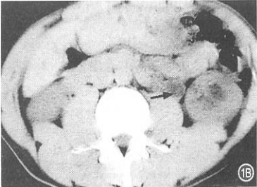

CT平扫见扩张的左输尿管内等密度结节(箭头处),增强扫描后期高密度管腔内低密度结节

CT或CTU:输尿管内软组织密度影,CT值40.1-43.8HU,增强轻度强化,梗阻以上输尿管、肾盂、肾盏扩张积水